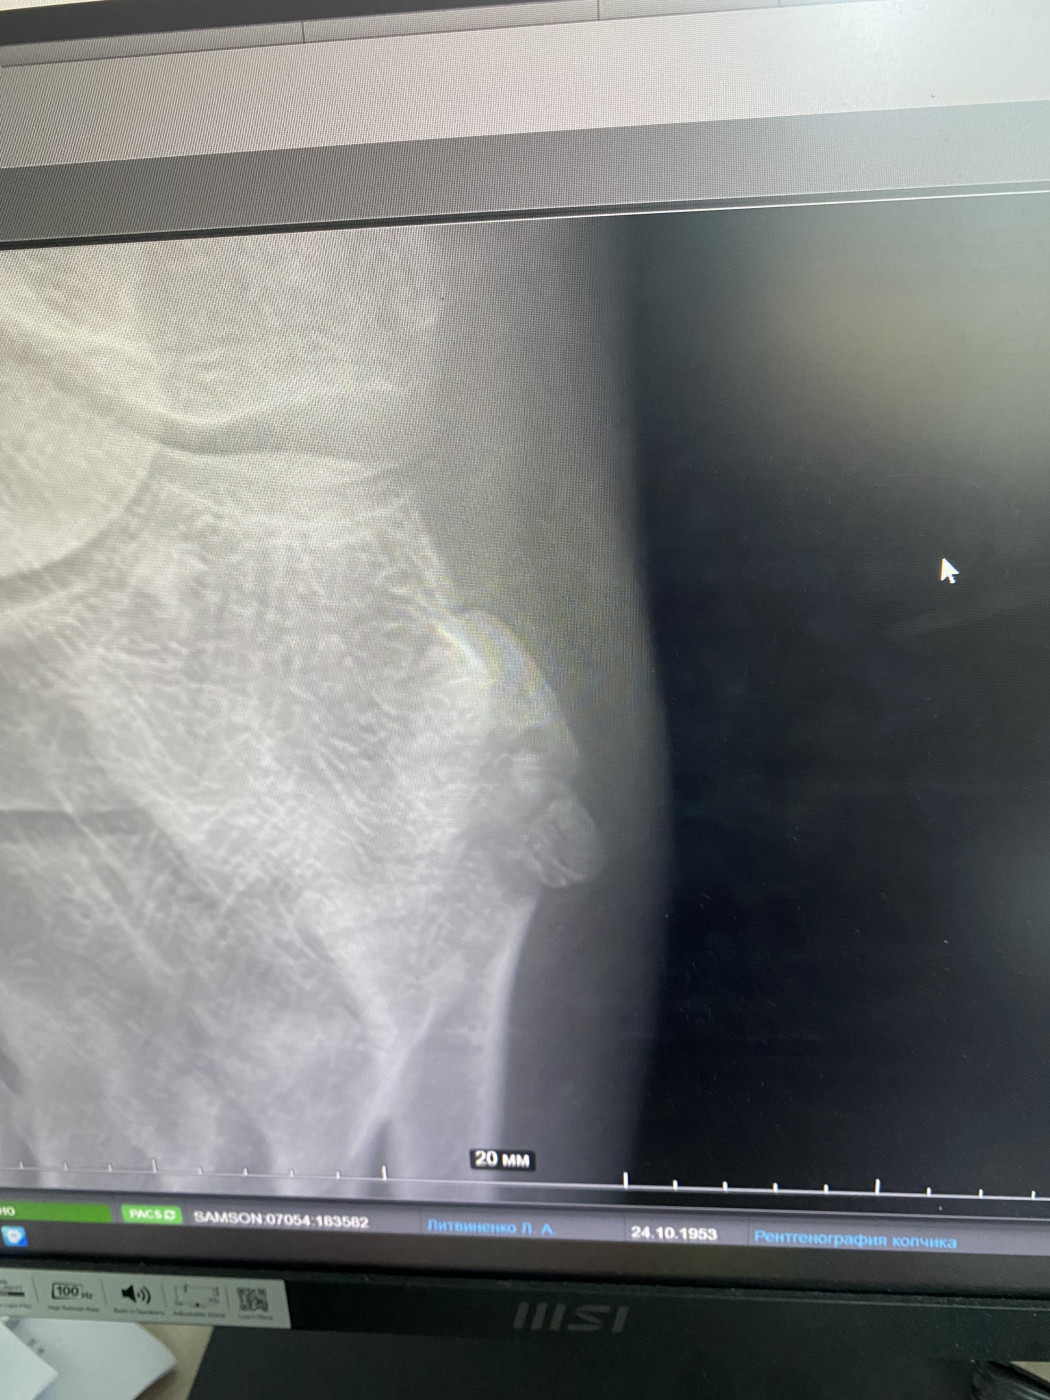

Расшифруйте снимок   2 ответа

Мой папа упал. Делали снимки и врач сказал, что он сломал, какую кость. Я не знаю, потому что его возил племянник. Подскажите пожалуйста что он сломал. Снимки прикладываю!